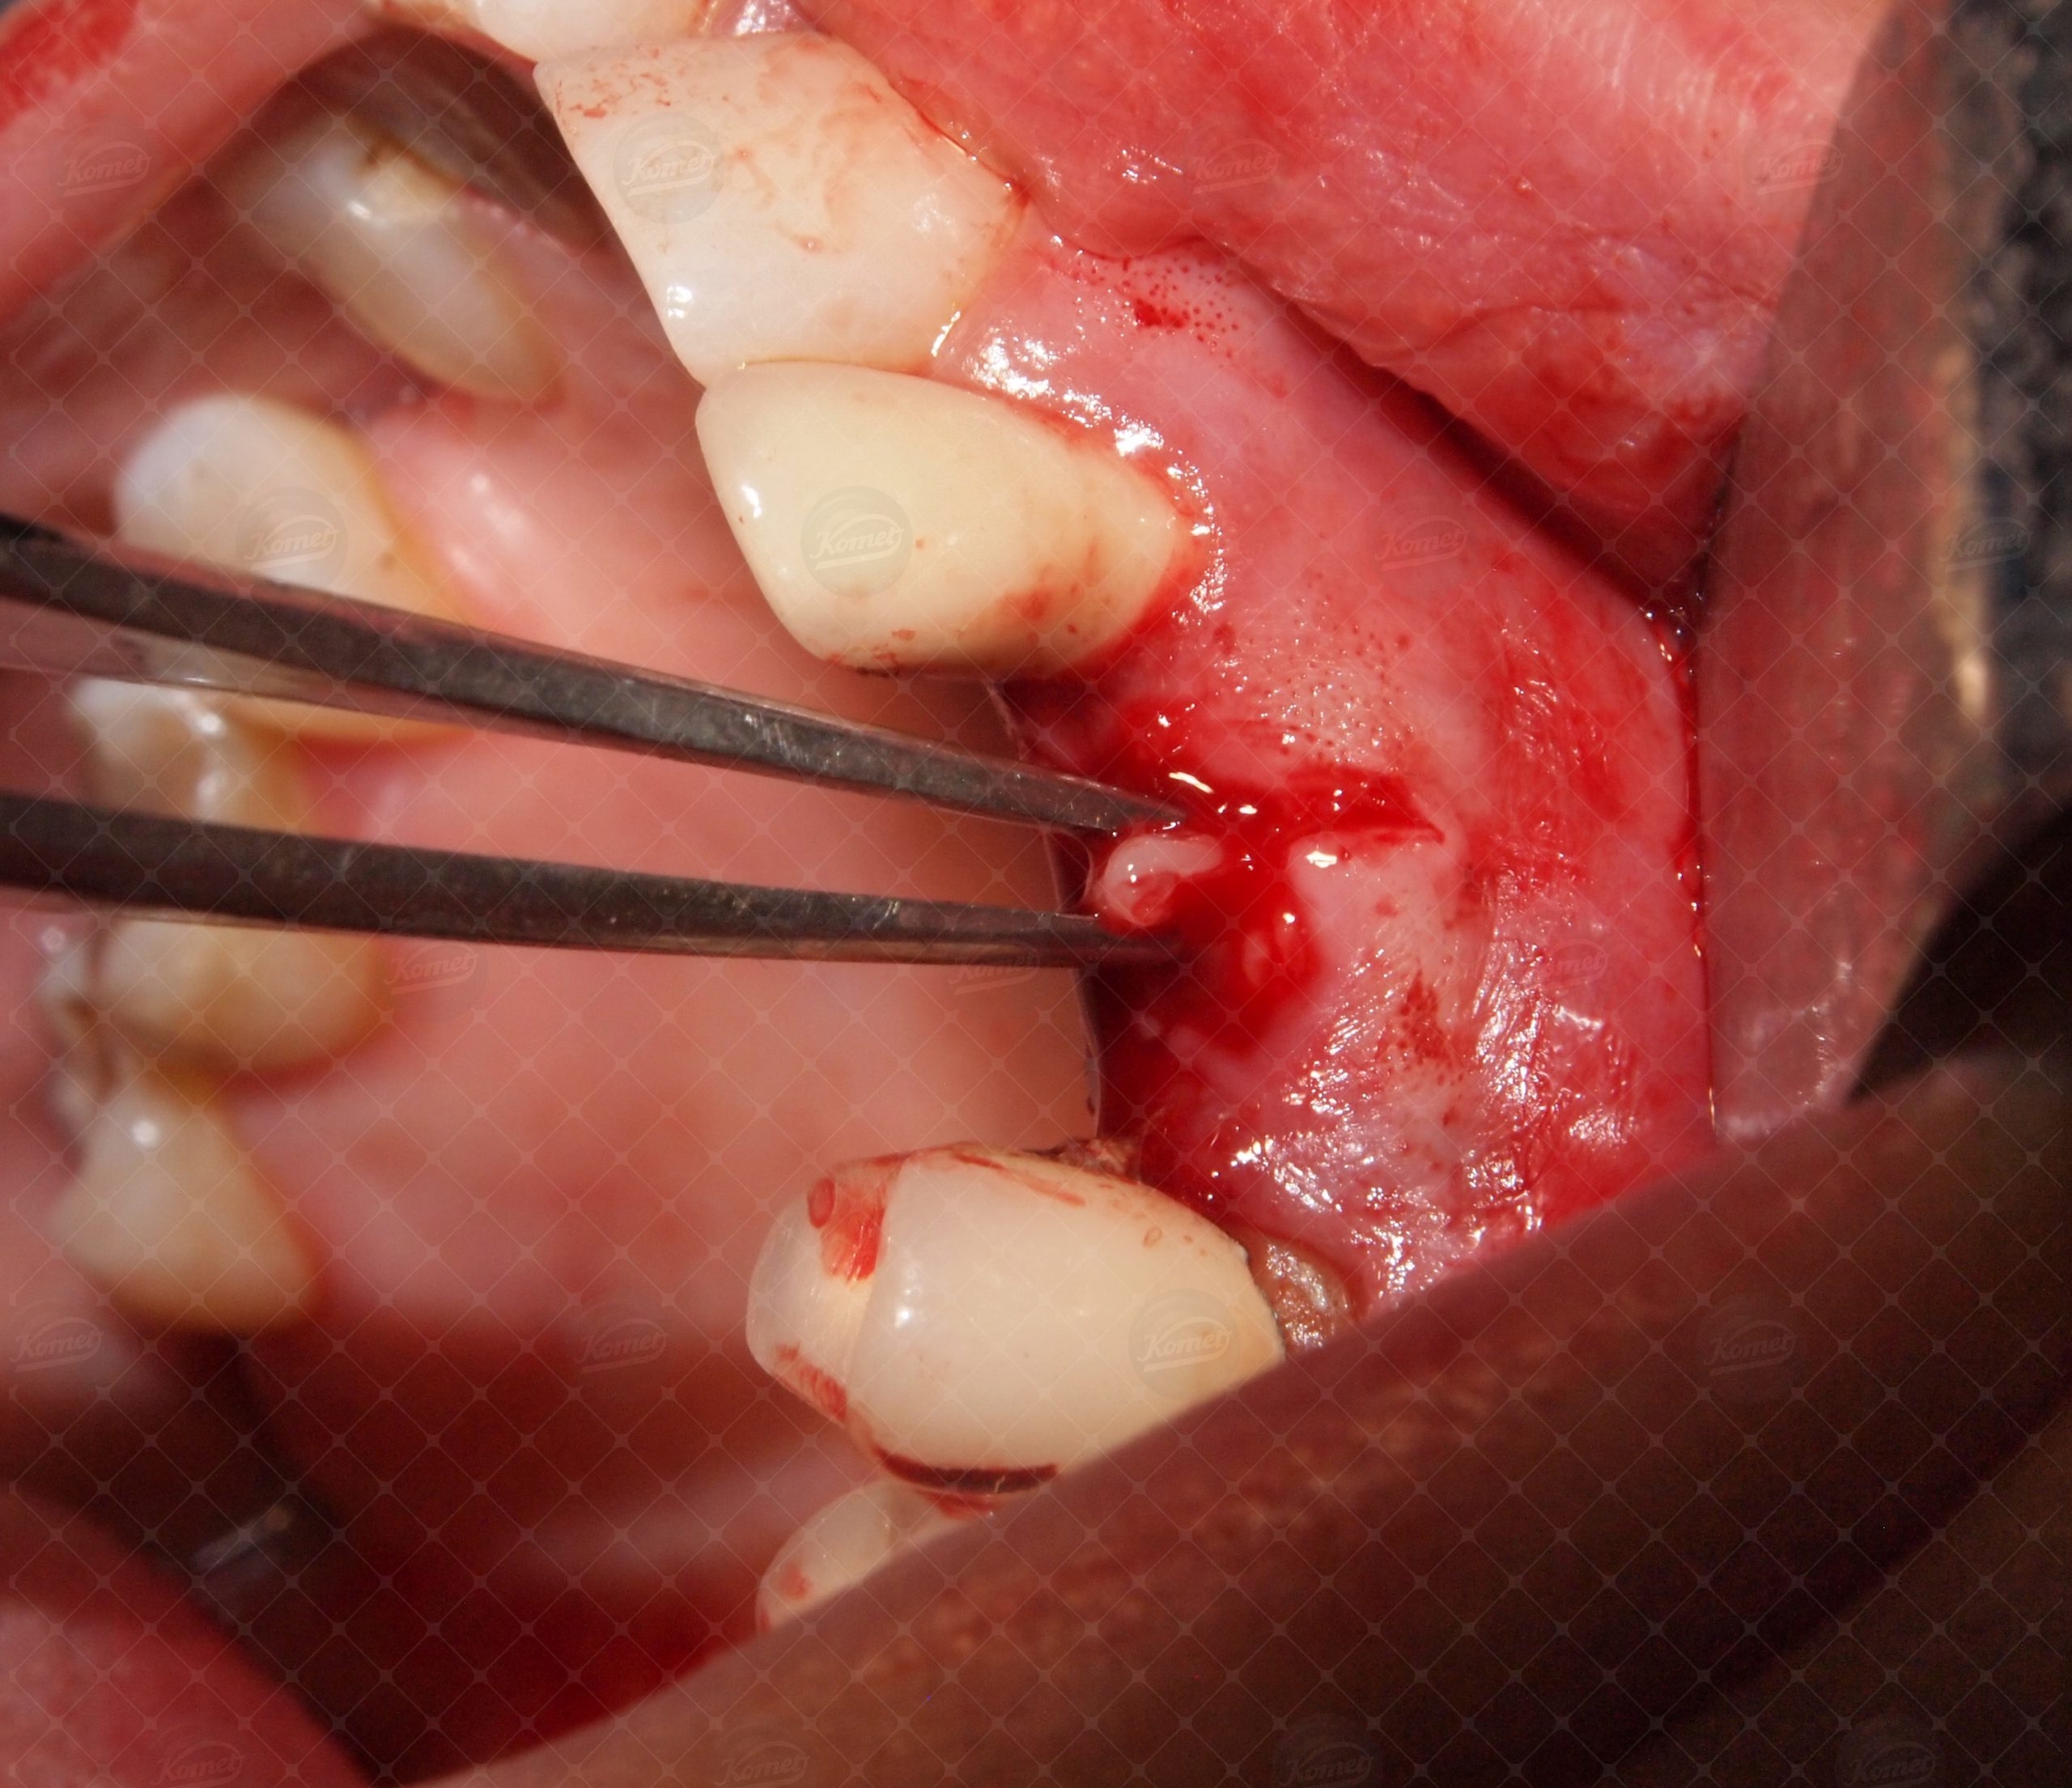

La gestione pre-estrattiva dei tessuti periradicolari è affidata ad inserti di tipo micro-saw SFS 100 ed SFS 101.

L’irrigazione ed il raffreddamento sono garantiti dall'utilizzo di soluzione fisiologica sterile portata sul sito chirurgico attraverso specifici raccordi (Komet SF1979).

Gli inserti opportunamente montati su di un manipolo sonico (Komet SF1LM) vengono utilizzati per le fasi di sindesmotomia (con livello di potenza 1-2) e micro-osteotomia (con livello di potenza 2-3). Il pretrattamento dei tessuti con strumenti sonici consente l’esecuzione di una estrazione minimamente invasiva, presupposto per la preservazione dell’alveolo post-estrattivo e della delicata parete ossea buccale.